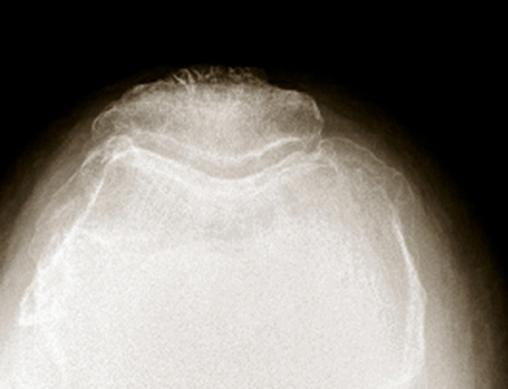

Radiologie d'une arthrose fémoro-patellaire. Sur les incidences axiales, on retrouve un amincissement ou une disparition de l’interligne externe, associés à une ostéophytose rotulienne trochléenne externe